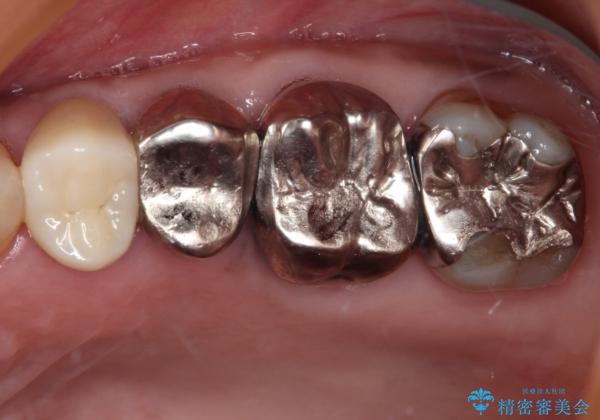

- 詰め物が欠けてしまい、虫歯かもしれないから診てほしいとのことで来院された患者様です。

精査の結果、詰め物の下に虫歯が大きく広がっているのがわかりました。

虫歯の範囲が大きく、部分的な詰め物では対応が難しいため、オールセラミッククラウンにて補綴することとしました。

また虫歯除去の際に、万一根管と交通してしまっても根管に感染を起こさないために、ラバーダム防湿をして虫歯除去しました。